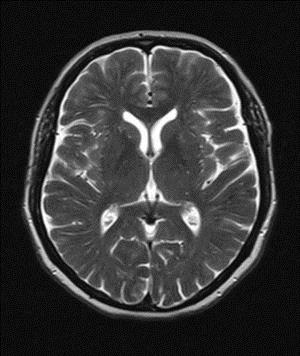

Кислородное голодание мозговой ткани в период внутриутробного развития или в ходе родового процесса сказывается на функционировании мозга в дальнейшем. У детей, перенесших состояние гипоксии, часто возникают неврологические нарушения и изменение структуры мозговой ткани, что обнаруживается в ходе нейровизуализации.

В ходе инструментальной диагностики выявляются внутрижелудочковые кровоизлияния, повреждение мозговой ткани ишемического генеза преимущественно перивентрикулярной локализации, отек мозга. Анализ крови показывает снижение уровня гемоглобина – анемию разной степени тяжести.

При обследовании головного мозга для скорейшего выявления атрофических очагов используется МРТ (магнитно-резонансная томография). Также могут применяться следующие методы диагностики: